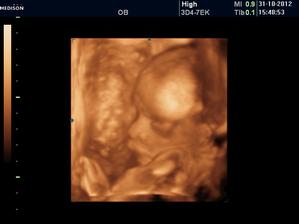

Nase tehulkovanie na druhu :o)))))